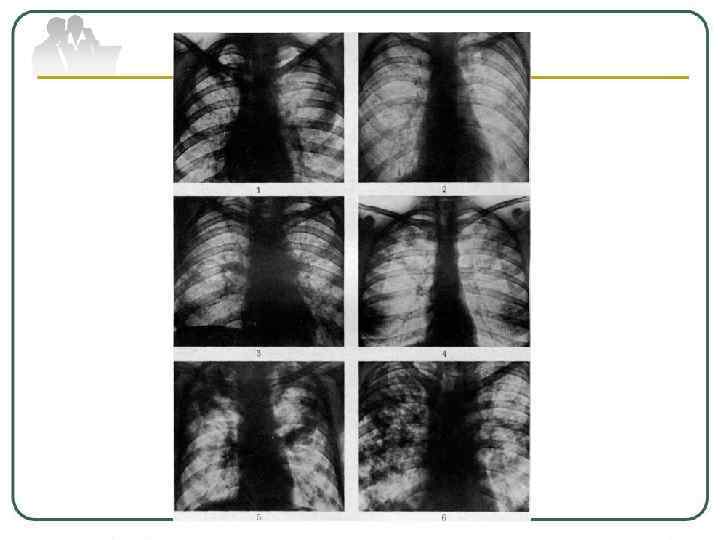

• Классификация Турбана—Герхарда (1902). была основана на так называемой апикокаудальной теории прогрессирования туберкулеза легких. • Считалось, что вначале туберкулезный процесс поражает легочные верхушки (I стадия), • затем распространяется на средние отделы легких (II стадия) и, наконец, поражает все легкое или оба легких (III стадия). Классификация Турбана—Герхарда была простой и подчеркивала роль распространенности процесса для прогноза болезни.

Однако последующие патологоанатомические и рентгенологические наблюдения показали несостоятельность апикокаудальной теории. Было установлено, что заболевание туберкулезом может начинаться и с нижних долей легких. Кроме того, течение процесса может быть сразу же тяжелым прогрессирующим. В связи с этим были предложены другие, более совершенные классификации туберкулеза.